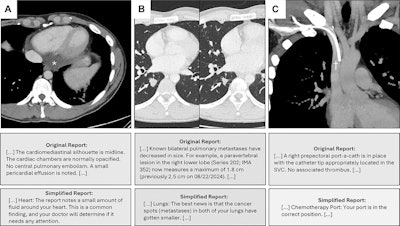

Chest CT images in a participant with metastatic nonseminoma, with relevant text from the original and simplified reports below each image (see Table S8 for the full reports). (A) Axial image shows pericardial effusion (*). (B) Axial images from a previous examination (left) and the current examination (right) show regressing pulmonary metastasis (arrow). (C) Coronal image shows right prepectoral port catheter with the tip in the superior vena cava (SVC) (†). This example does not contain errors in the text presented.Images and caption courtesy of the RSNA.